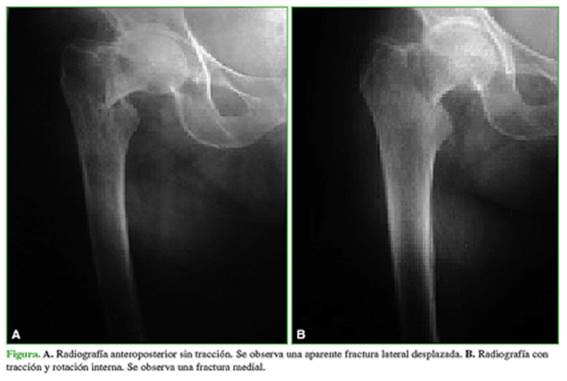

Por otro lado, nueve (17,6%) de las 51 respuestas cambiaron de una clasificación inicial correcta a una incorrecta al evaluar la radiografía con tracción y rotación interna: siete casos de fracturas intertrocantéricas inestables cambiaron a fracturas intertrocantéricas estables, un caso cambió de fractura intertrocantérica estable a fractura de cuello femoral desplazada (Figura) y un caso cambió de fractura de cuello femoral desplazada a fractura de cuello femoral no desplazada (Tabla 3).

Al evaluar los nueve casos (17,6%) en los que la radiografía con tracción y rotación interna cambió una respuesta correcta por una incorrecta, solo en dos pacientes, el cambio de respuesta hubiese tenido repercusión en la indicación del tratamiento: en un caso, porque la modificación fue de una fractura intertrocantérica estable a una fractura de cuello femoral desplazada (Figura) y, en el otro, de una fractura de cuello femoral desplazada a una fractura de cuello femoral no desplazada.